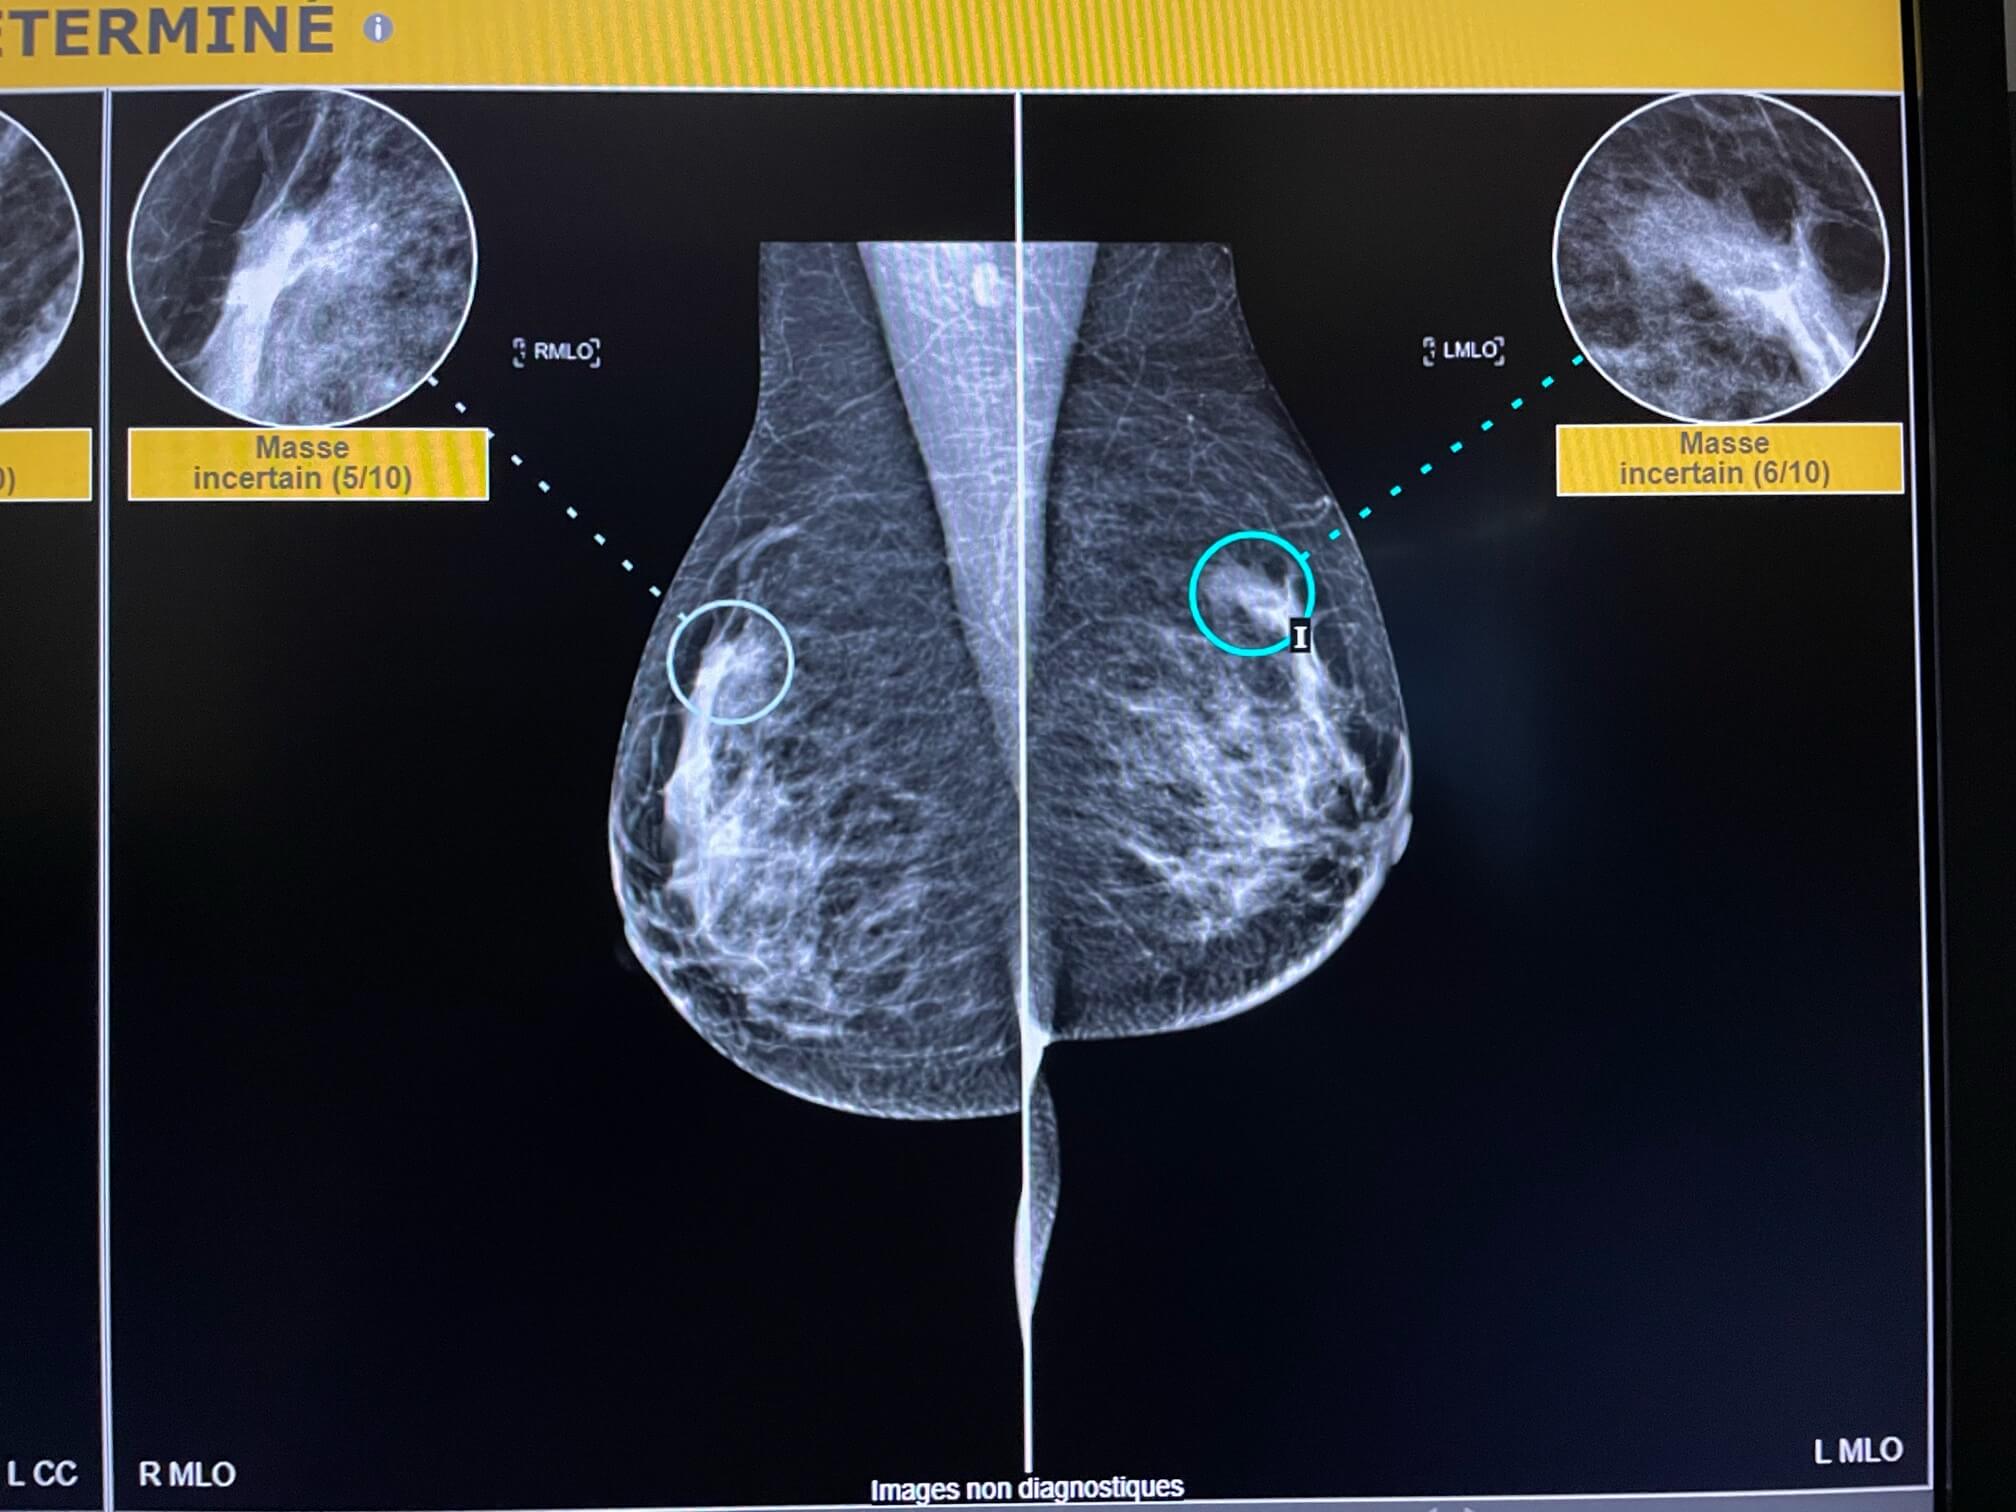

Femme de 51 ans, mammographie de dépistage.

MammoScreen™ pointe un surcroît d’opacité interne du sein gauche.